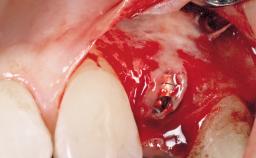

Surgical treatment of a 67-year-old male patient exhibiting an extended edentulous space in the anterior maxilla after the removal of three hopeless incisor teeth.

The video demonstrates implant placement using a surgical stent according to the principle of prosthodontically driven implant placement. The deficient ridge is augmented with locally harvested autologous bone chips, a superficial layer of xenogenic DBBM particles and a resorbable collagen membrane. The surgery is completed with a precise, tension-free primary wound closure.

Bone Volume Deficient horizontally, allowing simultaneous augumentation